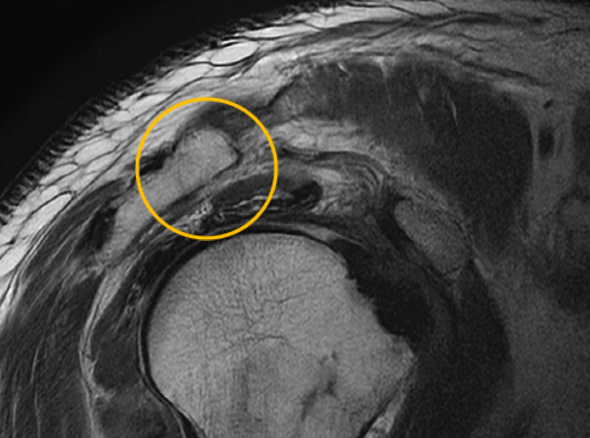

어깨충돌증후군이 발생하게 되면 회전근개에 염증이 발생하게 되고

급성 부종을 일으키게 됩니다.

관절 내시경을 통한

견봉 성형술

관절 내시경을 통하여

힘줄 손상을 유발하는 견봉하 골극을 제거합니다.